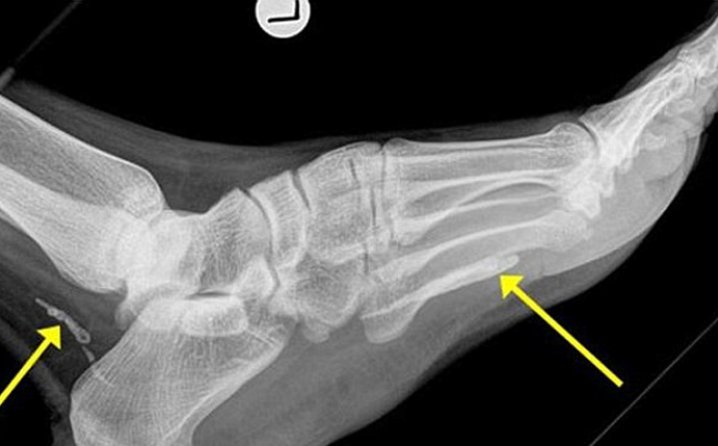

НЕОБИЧНИ ЛЕКАРСКИ СЛУЧАИ: По цели 36 години од жена извадиле скелет од фетус, израснат нос на грб, тинејџер имал 232 заби…

Жена на која ѝ израснал нос на `рбетот, тинејџер на кој му биле извадини 232 заби, жена која се родила без мал мозок, како и жена на која по цели […]